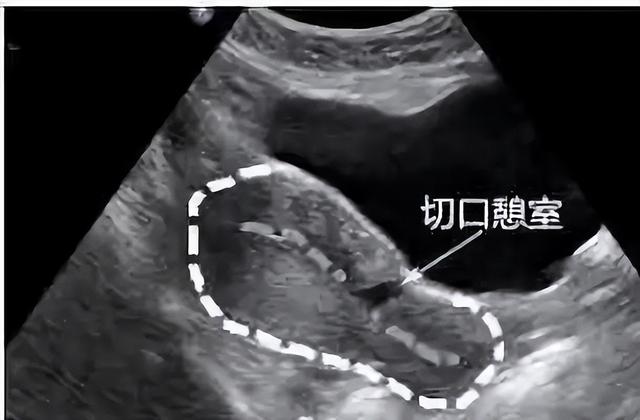

对于手术,我们老百姓有个俗称,叫「开刀」。既然是开刀自然会有一个切口,当剖宫产术后的子宫切口愈合缺陷时,切口处会出现一个与宫腔相通的凹陷,看起来好像一道沟,这个凹陷就是我们所说的憩室。

子宫切口憩室多位于子宫下段或峡部,少数位于宫颈上段,主要与原剖宫产切口部位及剖宫产时临床宫颈有无缩短或扩展有关,简单点说,它就像一间违章改建的“危房”。